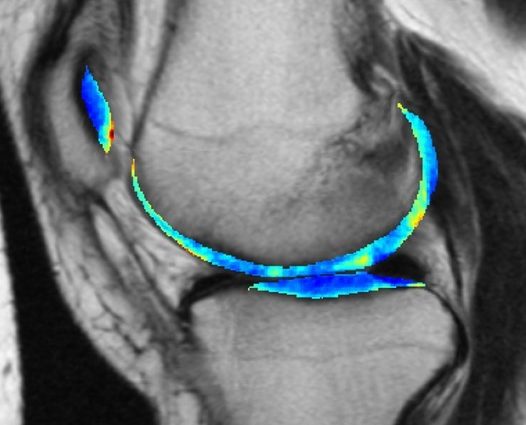

Attualmente l’osteoartrite si può rilevare con i raggi X, ma lo svantaggio è che si evidenzia quando purtroppo il danno alle cartilagini è già avvenuto. In questo studio i ricercatori hanno analizzato le immagini MRI del ginocchio di migliaia di pazienti per valutare come la malattia si evolve nel tempo.

Hanno quindi fatto imparare al software da loro creato quali erano i lievi segni di artrite in quei soggetti dove poi la malattia si è davvero sviluppata, escludendo invece quelli che non erano correlati a un futuro evolvere della patologia. Un’operazione che un essere umano non è in grado di svolgere, gestita quindi dall’intelligenza artificiale.

Il metodo è quindi stato testato su dozzine di pazienti presintomatici col risultato che è stato in grado di predire l’osteoartrite nel 78% dei casi tre anni prima dello sviluppo della malattia.